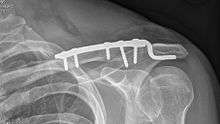

Osteosynthesis is the reduction and internal fixation of a bone fracture with implantable devices that are usually made of metal. It is a surgical procedure with an open or per cutaneous approach to the fractured bone. Osteosynthesis aims to bring the fractured bone ends together and immobilize the fracture site while healing takes place. In a fracture that is rigidly immobilized the fracture heals by the process of intramembranous ossification.